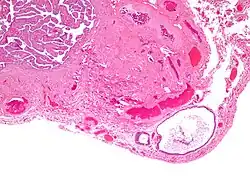

- Cyst (may also be solid nest) of transitional type epithelium.

- Eosinophilic luminal secretions.

Walthard cell rests, sometimes called Walthard cell nests, are a benign cluster of epithelial cells most commonly found in the connective tissue of the fallopian tubes, but also seen in the mesovarium, mesosalpinx and ovarian hilus.

They appear as white/yellow cysts or nodules that can reach a size of 2 millimeters. They typically have elliptical nuclei with a long groove (along the major axis) – so-called "coffee bean" nuclei.

It has been suggested that these cell rests are the histogenetic origins of Brenner tumors, due to the histological similarity of the epithelium of Walthard cell rests and Brenner tumors to the urothelium of the lower urinary tract. Also, it has been proposed that Brenner tumors and Walthard cell rests signify urothelial differentiation within the female genital tract.

High magnification micrograph of a Brenner tumor showing the characteristic coffee bean nuclei which are also seen in Walthard cell rests. H&E stain. High magnification micrograph of a Brenner tumor showing the characteristic coffee bean nuclei which are also seen in Walthard cell rests. H&E stain.